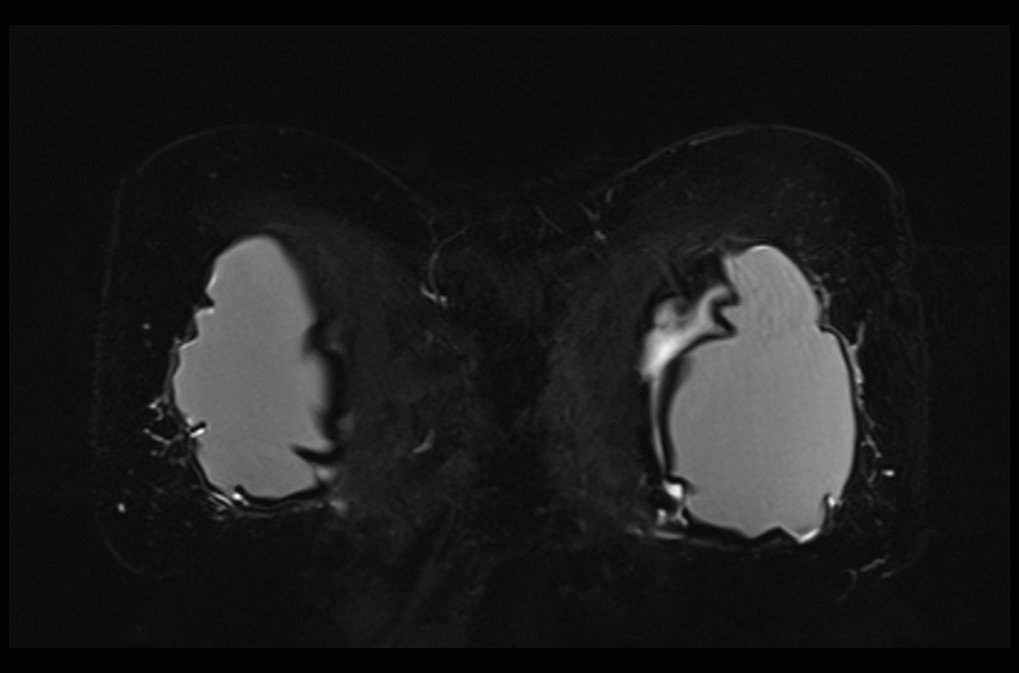

MRI breast implant stir coronal images 1 - MRI

MRI breast implant stir coronal images 2 - MRI

MRI breast implant stir coronal images 3 - MRI

MRI breast implant stir coronal images 4 - MRI

MRI breast implant stir coronal images 5 - MRI

MRI breast implant stir coronal images 6 - MRI